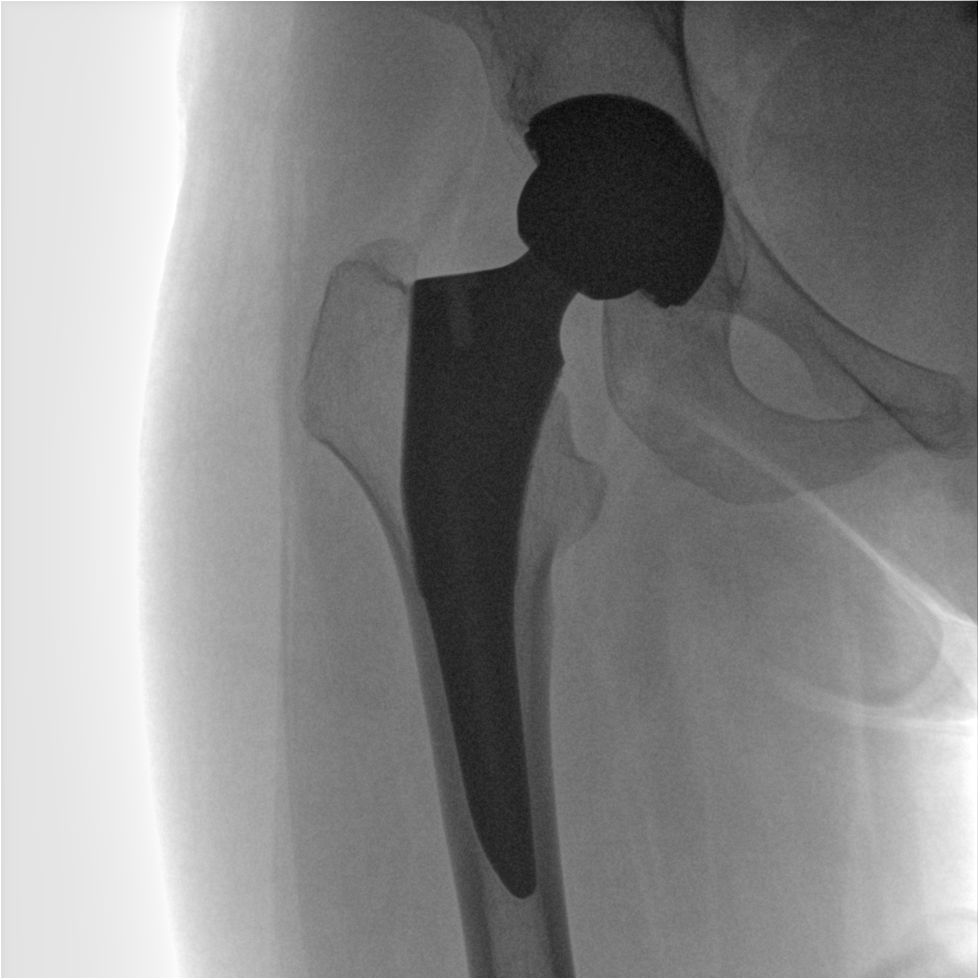

術(shù)中三維成像和橫斷面圖像提供多角度的手術(shù)診斷信息,輔助醫(yī)生進(jìn)行術(shù)中評(píng)估判斷,諸如骨折復(fù)位情況和內(nèi)植入螺釘?shù)某叽绾臀恢茫o助手術(shù)更好地完成。

提供更大的術(shù)中三維成像視野,采集更多圖像信息,可一次拍全全段頸椎、全段腰椎、七節(jié)胸椎、雙側(cè)骶髂關(guān)節(jié)、股骨頭及單側(cè)盆骨。